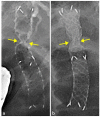

FIGURE 5

The notches immediately after deployment of the novel self‐expandable metal stent (SEMS) without fistula dilation and conventional braided fully‐covered SEMS with fistula dilation. The notch (arrows) in the novel SEMS. (a) is deeper and steeper than that in the conventional SEMS (b)